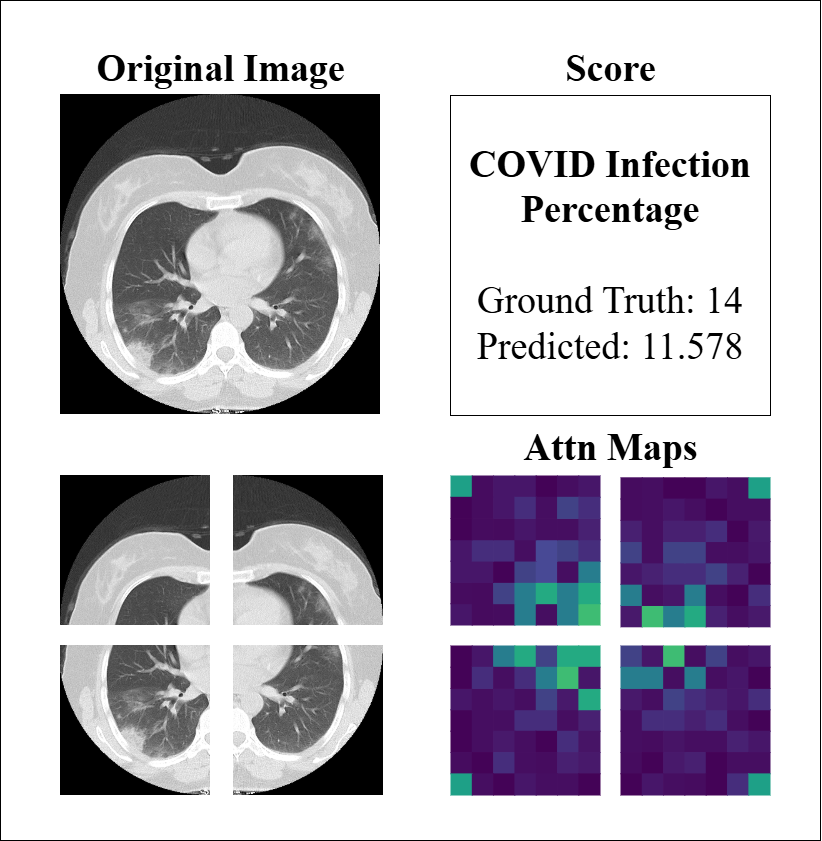

4.4 Model Interpretability

Similarly, to assess the model’s performance on CT imaging, we analyzed attention maps and prediction scores across representative cases, as illustrated in Figure 8. The examples demonstrate the model’s capacity to identify regions of COVID-19 involvement, with attention maps highlighting ground-glass opacities and consolidations that correlate well with infection percentage predictions in most cases (e.g., GT 60 vs. predicted 56.2). The spatial distribution of attention weights aligns with the predicted severity scores, reflecting the model’s ability to quantify disease burden through learned feature importance. However, the third example (GT 22 vs. predicted 6.4) reveals a substantial underestimation, despite attention maps showing patchy activations. This discrepancy may be attributed to CT-specific challenges such as partial volume effects, slice thickness variability, or subtle early-stage findings that complicate severity assessment. These observations emphasize that while the model effectively captures pronounced disease patterns, its performance may be limited by technical factors inherent to CT acquisition and early/mild disease manifestations.